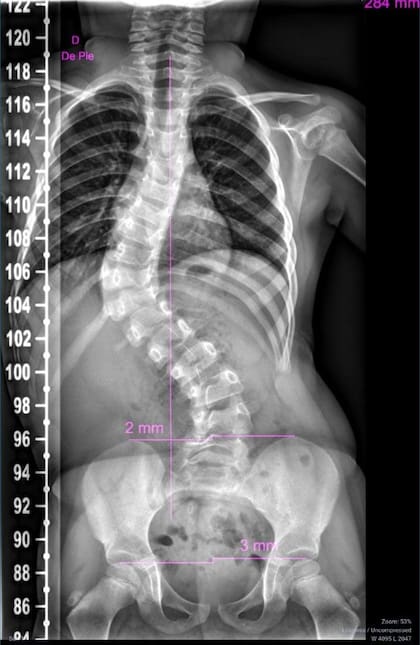

Cuenta que hace una semana le dieron un diagnóstico que volvió a sacudirla: “Tiene una angulación por escoliosis de 78 grados. Ya una de 50 grados se considera grave. No recomiendan la cirugía porque es muy pequeña; sí enyesarle la parte superior e ir cambiando el yeso cada tres meses. Eso hasta que se la pueda operar”.

Angustiada, subraya que a Pilar ya la operaron una vez, porque la cicatrización se había pegado a una costilla. “Va a rehabilitación desde siempre, pero al no tener ese lado del músculo, la columna se tuerce”, explica. Insiste en que su hija “se salvó de milagro. Está viva por un milagro y lo agradezco, pero ella nació sana”.

Hace una semana el médico que la atiende en el Hospital de Niños le precisó que la escoliosis de la nena es “grave; que hay que colocarle un yeso en su parte superior, que le dejarán un hueco en la panza para que pueda comer. Que no podrá bañarse. Se irá cambiando cada tres meses hasta que tenga edad para operarse. Y va a tener varias cirugías a lo largo de su vida. No me dijeron mucho más, me mandaron a sacar turno a Servicios Sociales para que me tramiten la vendas que necesitan para ponerle el yeso”, detalla María sobre esta nueva etapa.